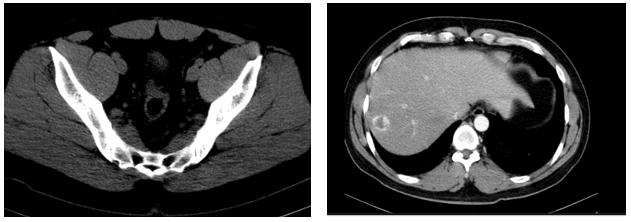

-        Chụp cắt lớp vi tính ổ bụngNốt đặc xương thân -cánh trái xương cùng kích thước 15x8mm và xương cánh chậu trái kích thước 13x9mm. Hình ảnh theo dõi u máu gan phải/ gan nhiễm mỡ

Hình 5: hình ảnh chụp cắt lớp vi tính ổ bụng sau điều trị 10 tháng không có tổn thương nghi ngờ thứ phát